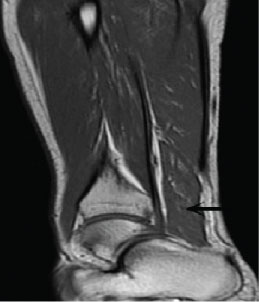

The MRI examination was performed using a 1.5-T MRI unit Signa Advantage Horizon; GE Medical Systems, Milwaukee, WI, USA. The T1 weighted coronal sequences showed the mass originating from the ventral portion of the normal soleus muscle and inserting to the medial surface of the calcaneus independently of Achilles tendon (Figure 1). Compared with the normal side, the affected side showed a homogeneous soft tissue mass located posteromedial to the flexor hallucis longus tendon and anteromedial to the Achilles tendon in all sequences (Figure 2, Figure 3 and Figure 4). It showed iso intense signal on all sequences (Figure 2, Figure 3 and Figure 4). And the pre-Achilles' fat pad was compressed by this muscle mass. The T1-weighted sequences showed a thin rim of adipose tissue within the fascial plane around the mass (Figure 1).

Figure 1: The T1 weighted sagittal sequence shows the mass (arrow) originating from the ventral portion of the normal soleus muscle and inserting to the medial surface of the calcaneus independently of Achilles tendon. View Figure 1